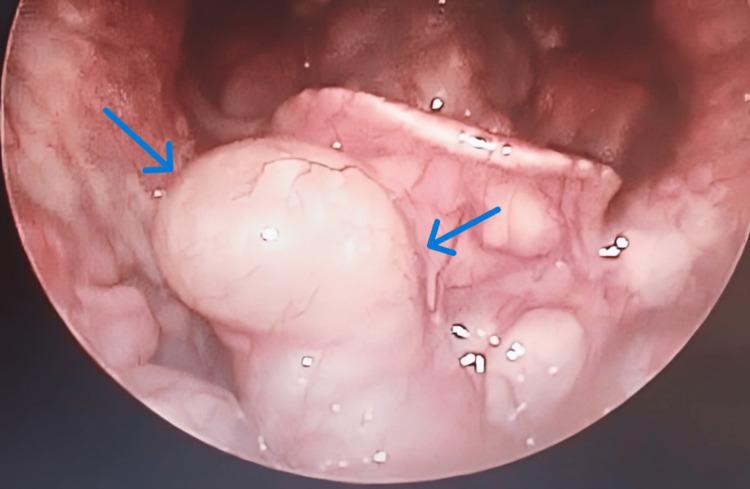

Vallecular cysts (VCs) are rare benign lesions arising from the obstruction of mucous gland ducts. VCs are uncommon anomalies found in both pediatric and adult populations. They are also known as mucous-retention cysts, preepiglottic cysts, ductal cysts, base-of-tongue cysts, and epiglottis cysts. VCs are often asymptomatic in adults and may present with nonspecific symptoms such as globus sensation, voice changes, dysphagia, hoarseness, or airway obstruction when symptomatic. This case report details a rare occurrence of a giant VC in an adult male, emphasizing the diagnostic approach and surgical management and highlighting the importance of managing the airway in such cases and the advantages of endoscopic procedures.

会厌谷囊肿(VCs)是由黏液腺管阻塞引起的罕见良性病变。VCs在儿童和成人中均为不常见的异常情况。它们也被称为黏液潴留囊肿、会厌前囊肿、导管囊肿、舌根囊肿和声门上囊肿。VCs在成人中通常无症状,有症状时可能表现为咽部异物感、声音改变、吞咽困难、声音嘶哑或气道梗阻等非特异性症状。本病例报告详细介绍了一名成年男性罕见的巨大VCs病例,强调了诊断方法和手术管理,并突出了在此类病例中气道管理的重要性以及内镜手术的优势。